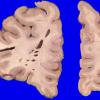

Artifact - Swiss Cheese Brain (2)